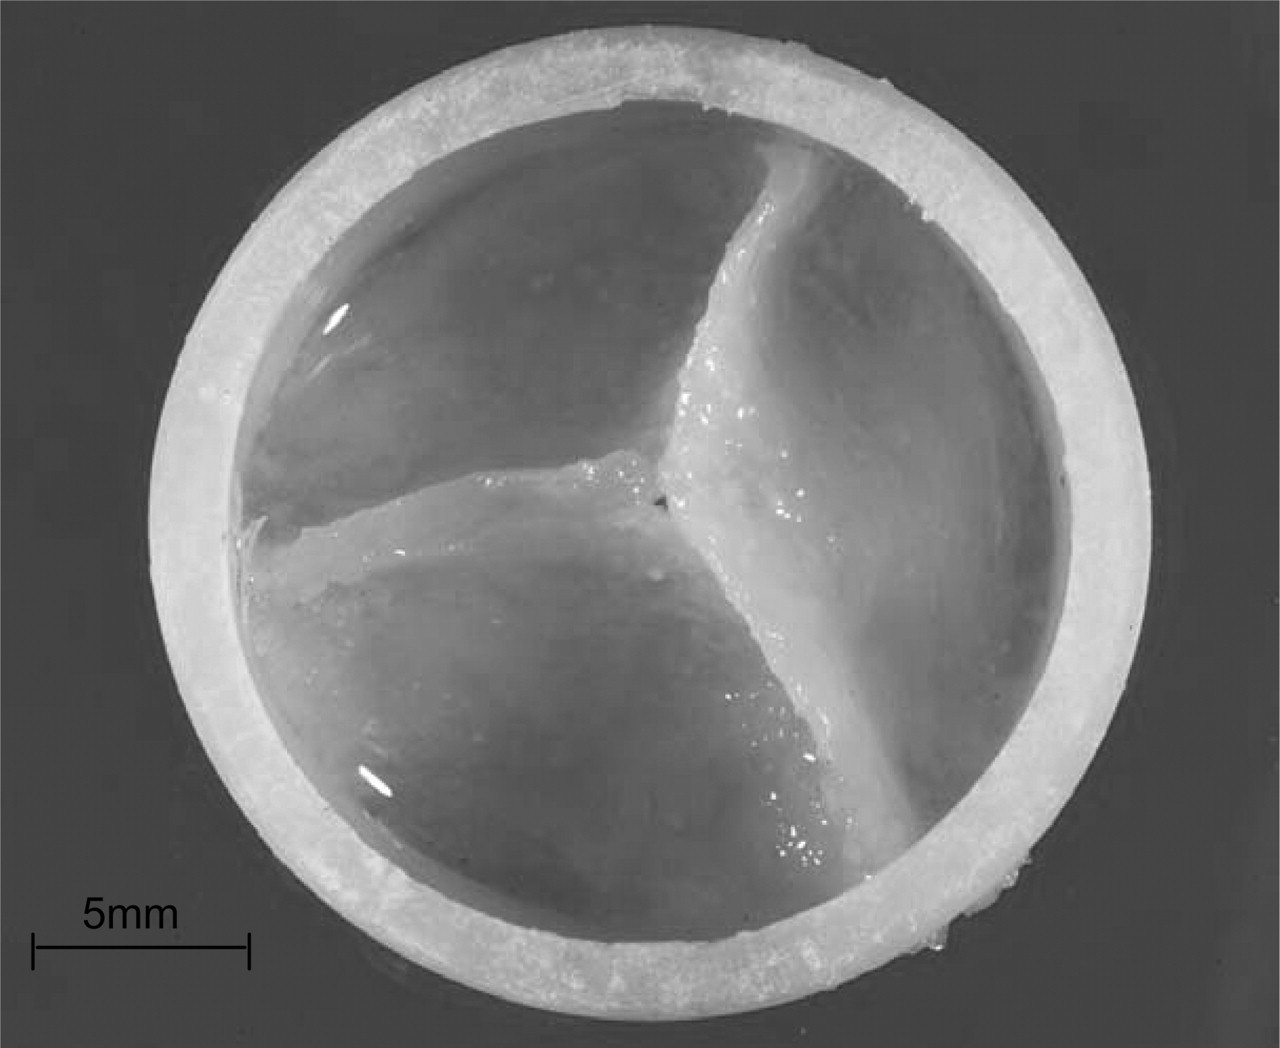

Transcatheter aortic valve implantation (TAVI) is a great alternative treatment option in high surgical risk and inoperable patients with severe symptomatic aortic stenosis (AS). TAVI is a rapidly emerging technique with a constantly expanding body of evidence. However, the devices, which are commercially available and are currently used widely, have several major limitations. In particular, the inability to reposition/ retrieve/ resheath valves, in addition to several patient selection and procedural limitations, such as the occurrence of moderate to severe paravalvular regurgitation (PVR), the risk of annular rupture, atrioventricular (AV) conduction abnormalities with subsequent pacemaker requirement, vascular complications and associated bleeding, coronary ostial obstruction by the valve, stroke, as well as complex delivery processes, are expected to be overcome with the newer generation valves. Consequently, a number of new transcatheter valve choices have been developed either for clinical study or are in the pipeline, that it is hoped to bring meaningful clinical outcomes compared with the currently commercially available technology. Early data on design modifications have shown significant reductions in adverse outcomes from TAVI.